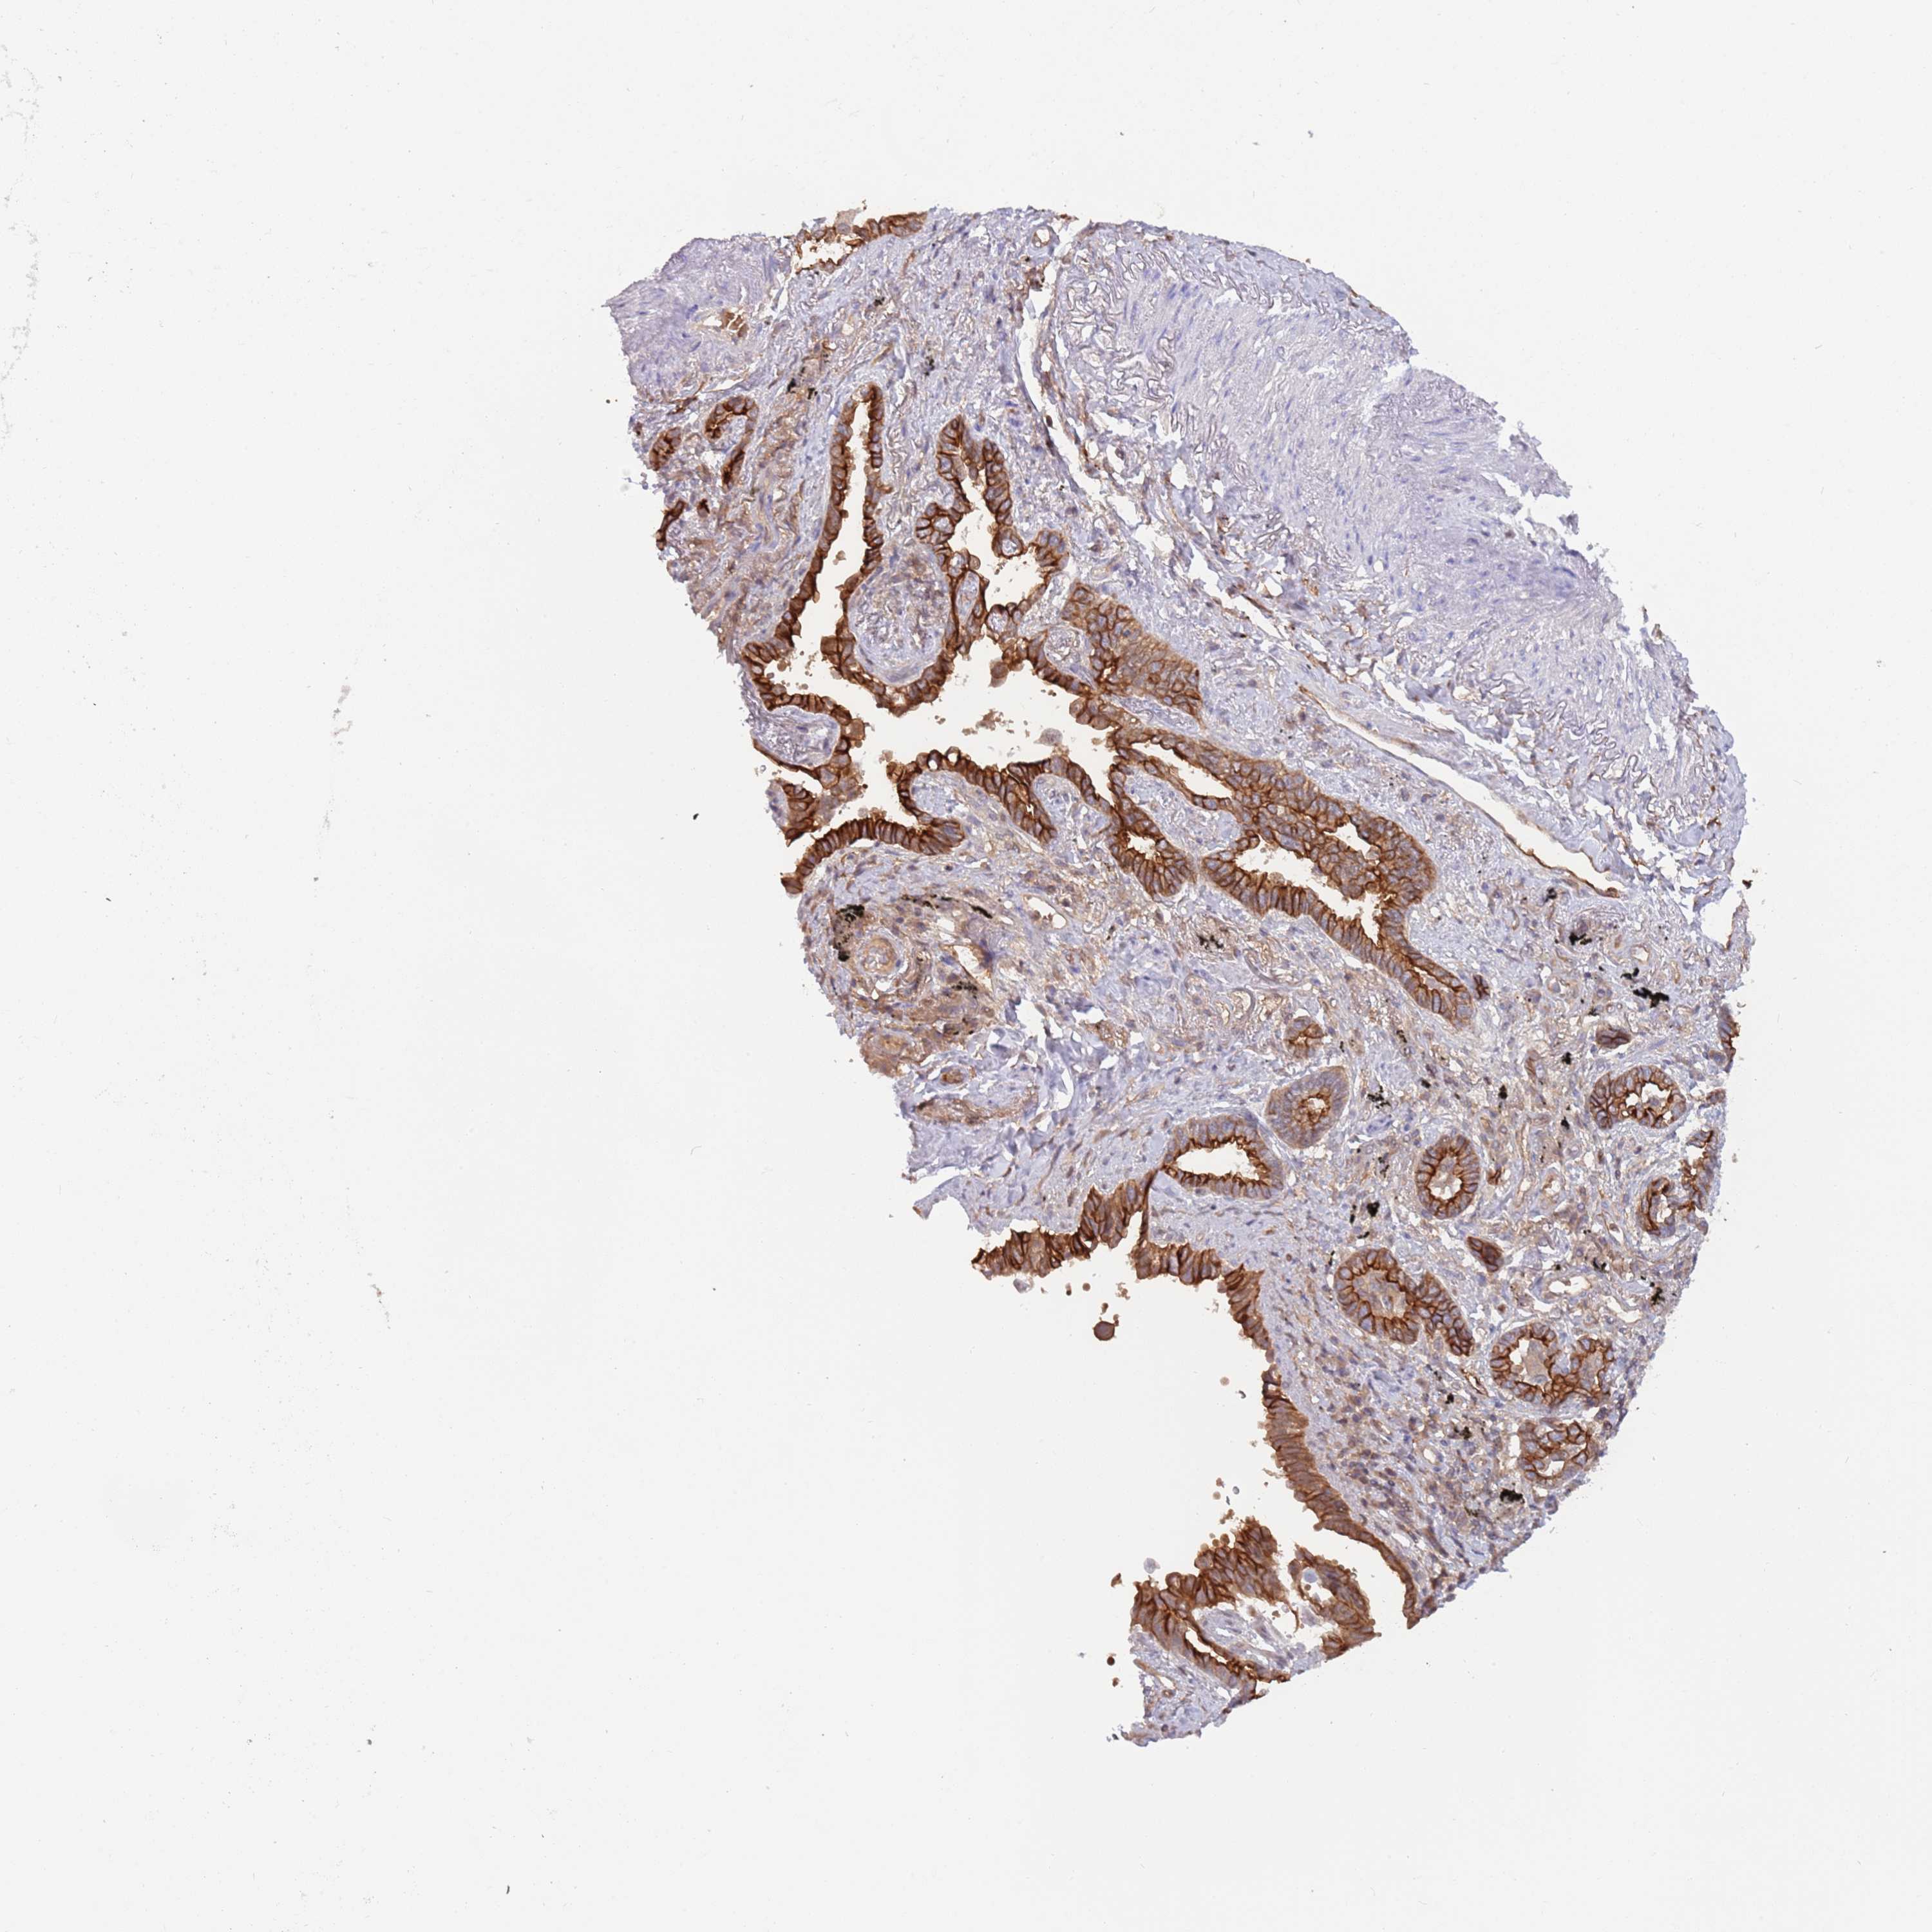

CANCER LUNG CANCER Show tissue menu

LUAD TCGA LUAD VALIDATION LUSC TCGA LUSC VALIDATION PROTEIN LUAD CPTAC PROTEIN LUSC CPTAC PROTEIN EXPRESSION

ANTIBODIES

AND

VALIDATION